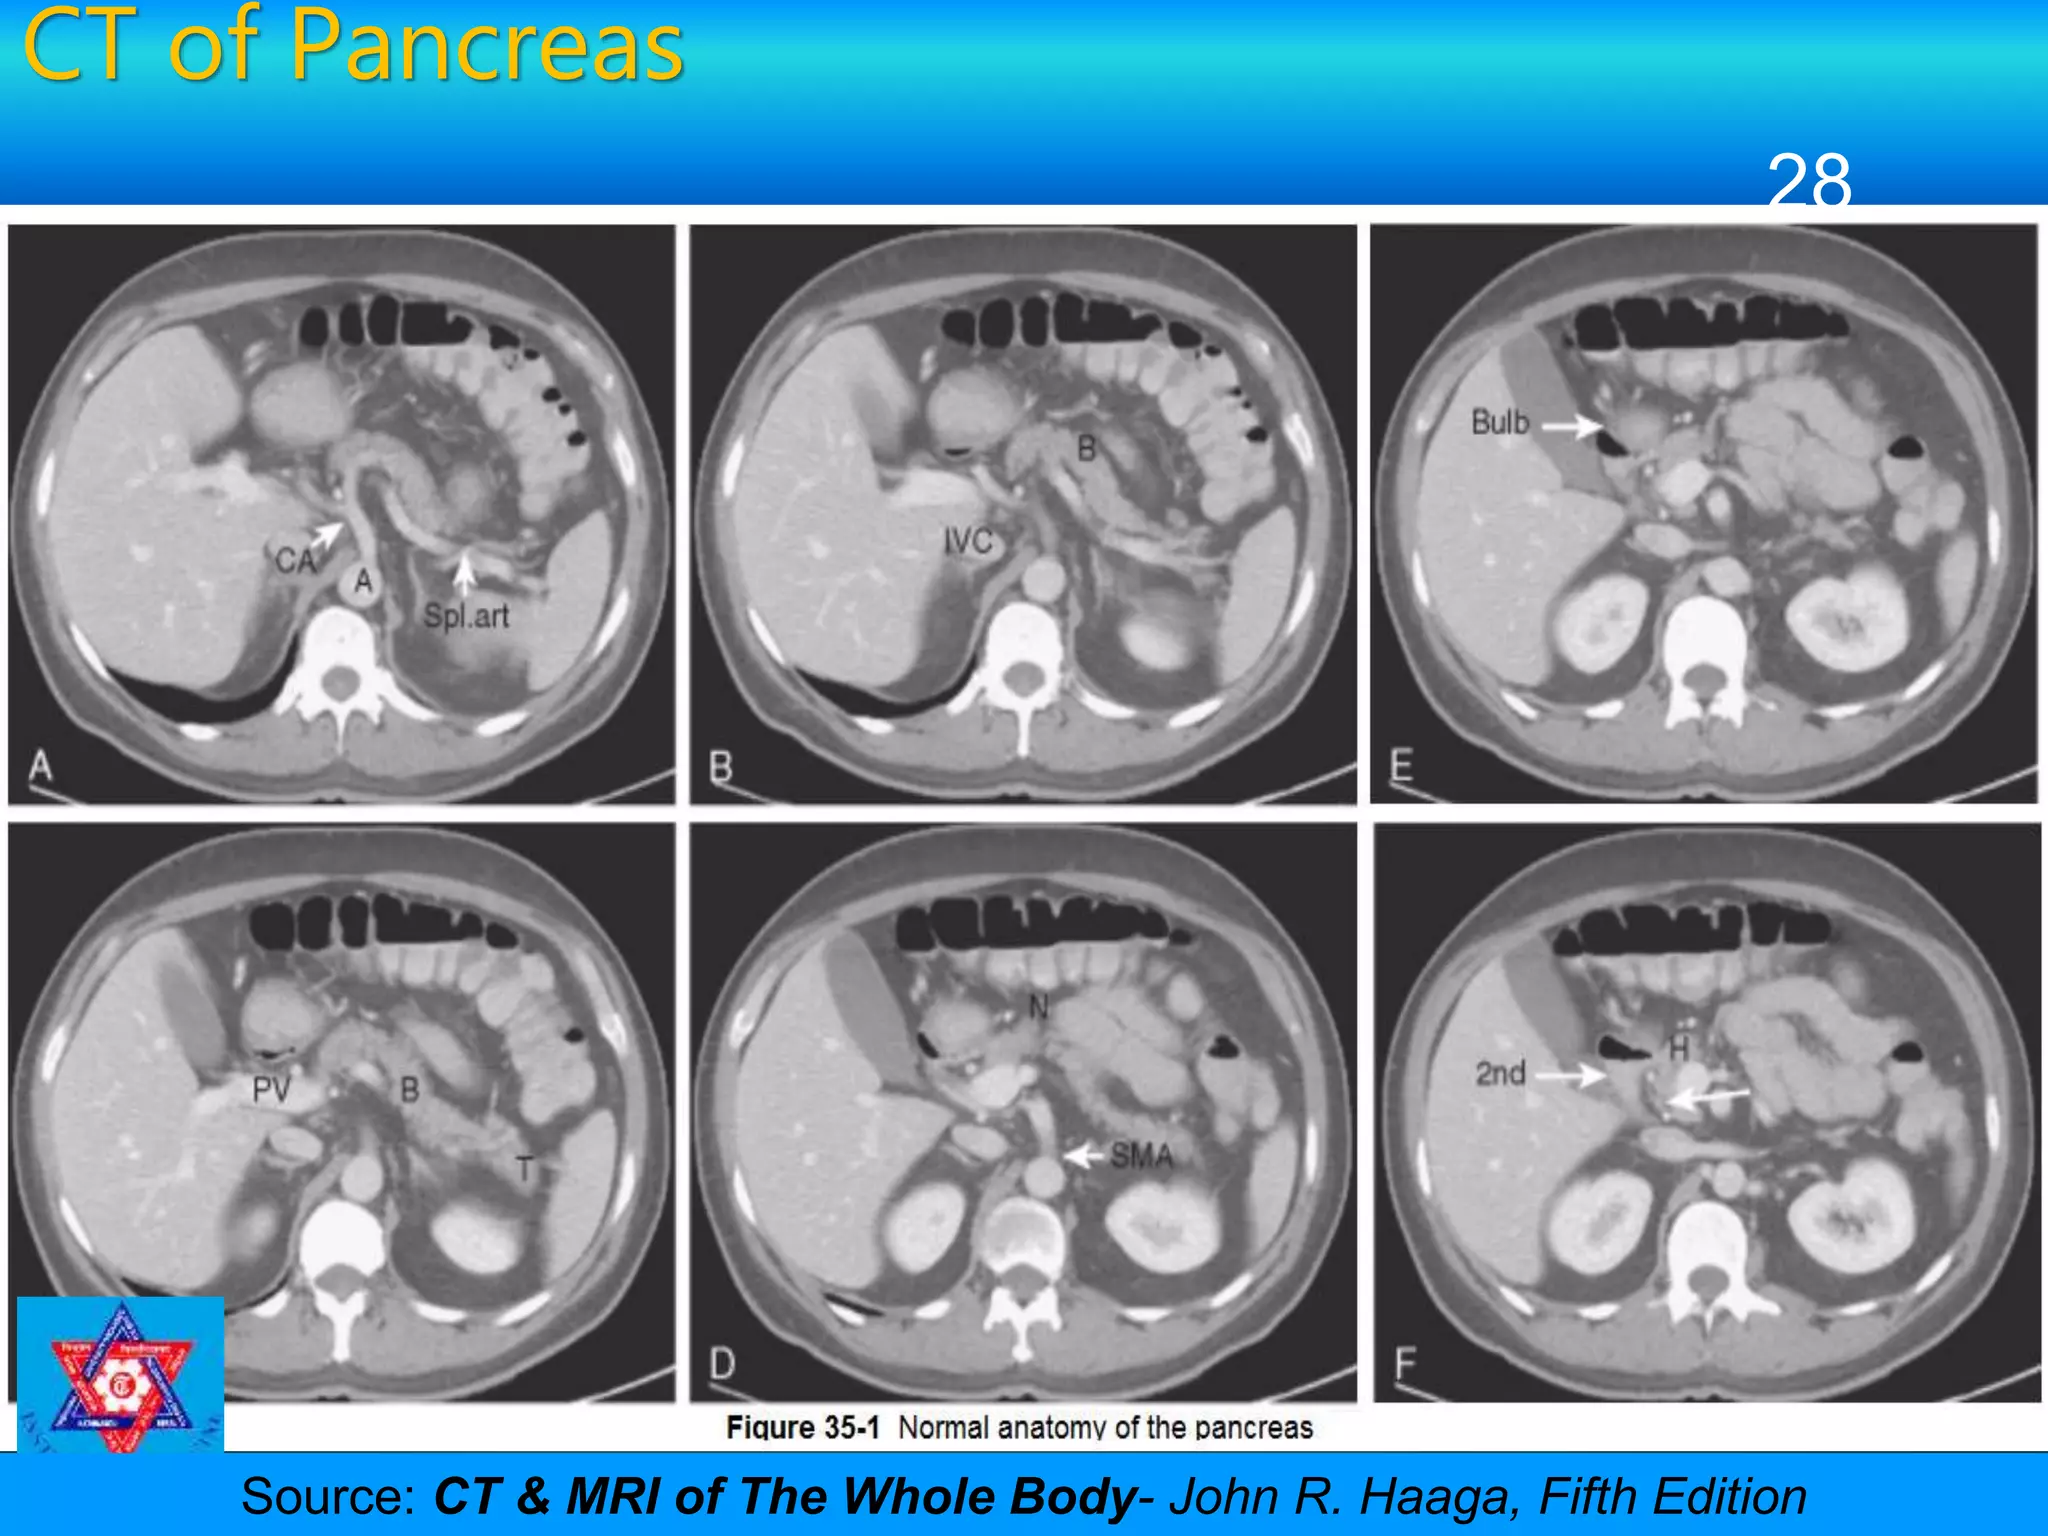

CT of Pancreas

28

Source: CT & MRI of The Whole Body- John R. Haaga, Fifth Edition

• #29 Figure 35-1  Normal anatomy of the pancreas. A to I, Axial CT sections of the pancreas from superior to inferior. A and B, Superior portion of the body of the pancreas (B) with the splenic artery (Spl.art) posterior to the body. The splenic artery is a branch of the celiac artery (CA), which in turns arises from the aorta (A). IVC, inferior vena cava. C and D, The oblique orientation of the long axis of the pancreas is seen with the tail (T) extending from the hilum toward the midline of the body (B). The body continues as the neck (N) anterior to the portal vein (PV) and superior mesenteric artery (SMA), which in turn continues as the head. E and F, The head lies in the C loop of the duodenum, bound superiorly by the bulb and medially by the second part of the duodenum (2nd). The common bile duct is seen as a low-density structure posterior to the head (H) of the pancreas (arrow in F). Branches of the pancreaticoduodenal arcade are seen around the head of the pancreas. G and H, The head lies anterior to the inferior vena cava (IVC) and is bound medially by the superior mesenteric vein (SMV). The head turns around and inferiorly to the triangular uncinate process (U), which lies posterior to the superior mesenteric artery (SMA) and vein. I, The inferiormost portion of the uncinate process is seen anterior to the superior mesenteric artery and vein.